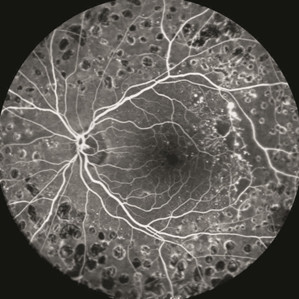

In the article “Managing diabetic eye disease eased with repeatable, high-quality imaging” recently published in Modern Retina, Dr. David Eichenbaum highlights various SPECTRALIS multimodal imaging platform features and their benefits in managing diabetic eye disease. He delves into the importance of having dependable and consistent imaging capability within the retina practice.

Managing Diabetic Eye Disease